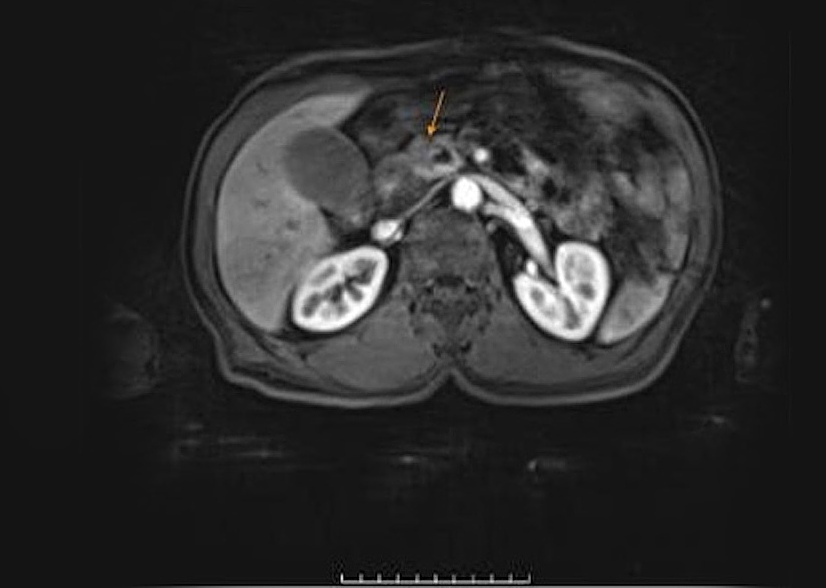

After several weeks of medication for elevated liver enzymes, Mr. Quang's skin and eye whites turned yellow, prompting him to visit Tam Anh General Hospital, TP HCM. Tests revealed his liver enzymes were 30 times higher than normal, with ALT (GPT) reaching 1,600 U/L (normal is around 50 U/L). A CT scan of the pancreas and an abdominal MRI identified a lesion approximately 20 mm in size in the head of the pancreas. This lesion was compressing and invading the pancreatic duct, which was dilated to 7 mm. The gallbladder wall was edematous, and the common bile duct was dilated both inside and outside the liver.

Abnormal lesion in the head of the pancreas on CT scan. Photo: Tam Anh General Hospital